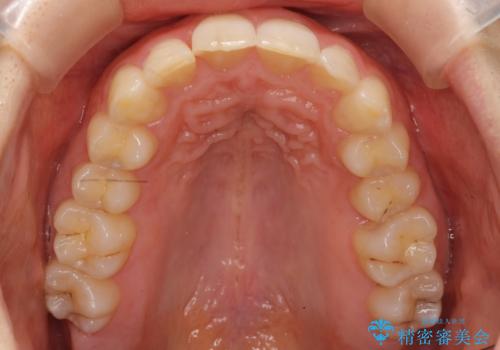

- 前歯のがたがたと出っ歯を主訴に来院。

CTを撮影したところ、臼歯部の頬側の骨の厚みが非常に大きく、通常では考えられない量の歯列の拡大が可能でした。

今回は健康を損なわずに非抜歯で治療が可能でしたが、

歯ぐきや骨の厚みが薄い他の患者さんでは難しいです。

左上5は180度捻転していましたので、そのまま並べています。

遠心移動などは行わず、IPRと拡大のみで治療を行いました。